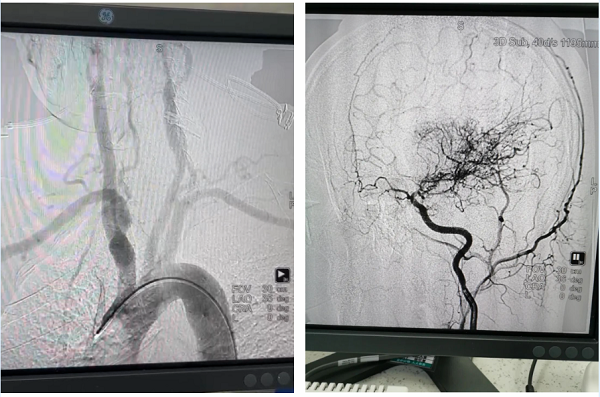

病例:患者男性,67岁,诊断“脑梗死、高血压、糖尿病、冠心病”,颈动脉彩超提示左侧颈动脉起始段狭窄,为进一步明确脑血管情况,预行脑血管造影;患者同时合并冠心病,提出希望能在脑血管造影同时,同台行冠脉造影明确心脏血管情况;为满足患者需求,我院神经内科立即请心血管内科医师会诊评估,最后决定为患者同台行冠脉及脑血管造影,造影顺利完成,精准评估了患者心脑血管狭窄程度,制定后期治疗计划,造影耗时约1.5小时,患者及家属非常满意。

心脏与脑血管造影手术是一种先进的影像学检查技术,通过向血管内注入造影剂,使心脏和脑血管显影,从而动态清晰地显示血管的形态、结构和血流情况。这种技术对于诊断血管狭窄、阻塞、动脉瘤等病变具有重要意义,并为后续的治疗提供精确的指导。